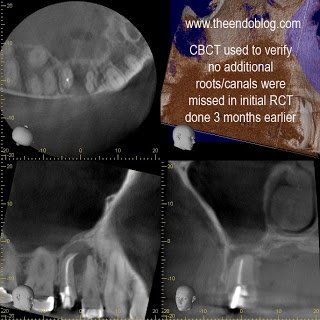

CBCT taken to evaluate the root morphology. It is clear that this is a single root/canal. (The canal has an oblong shape) It was chosen to treat this tooth with apical surgery to preserve the restorative work that has been completed and assure that the overextened gutta percha is removed.